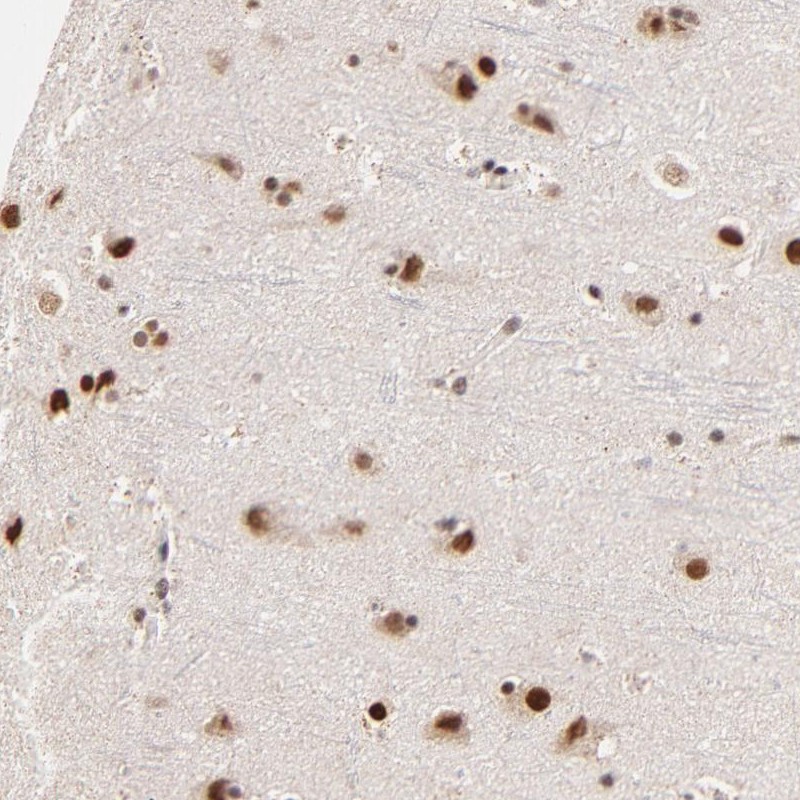

Immunohistochemical staining of human cerebral cortex shows strong nuclear positivity in neuronal cells and glial cells.